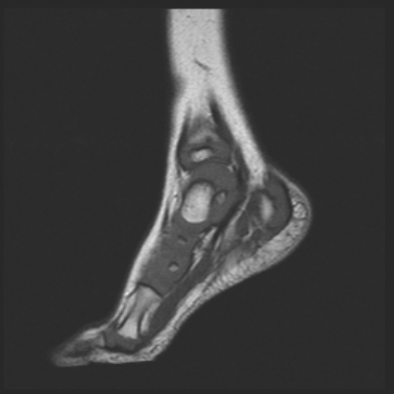

Irina Trifonova, MD; Magda Mendez, MD, FAAP; Nithi Fernandes, MD; July K. Jean, MD; Laura Castellanos, MD

A previously healthy 18-month-old boy presented to the emergency department (ED) with a chief complaint of a 1-day history of refusal to bear weight on his left foot.